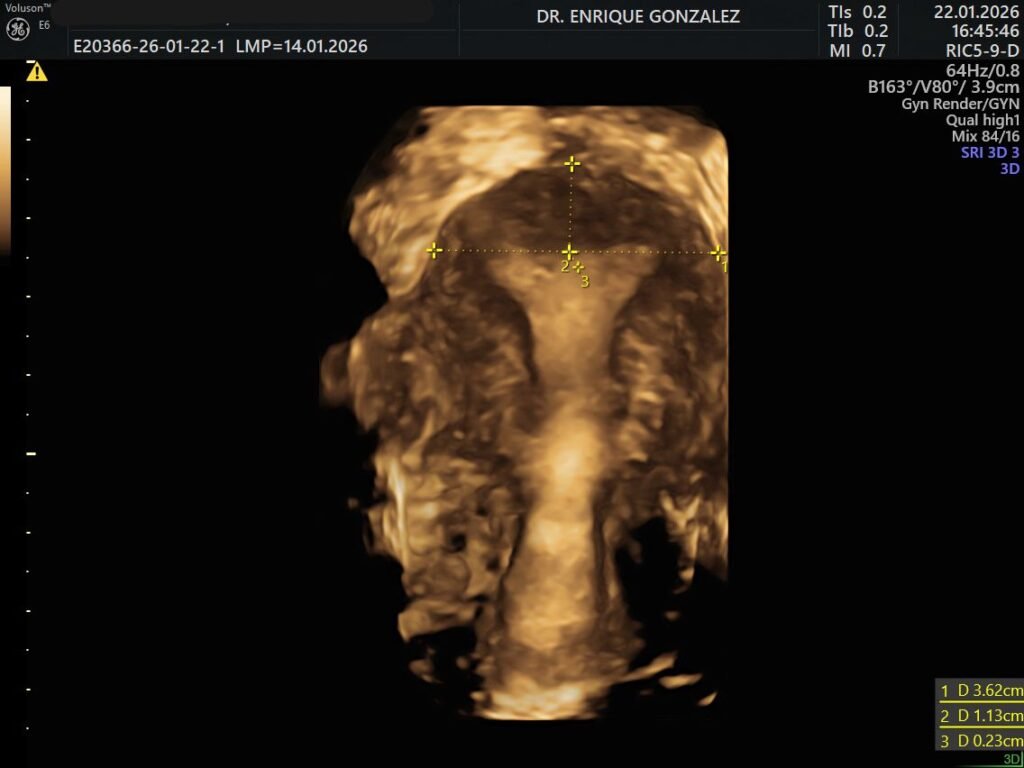

Dr. Enrique Gonz谩lez L贸pez

Especialidad en Ginecolog铆a y Obstetricia.